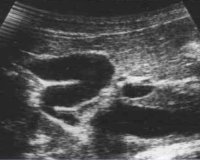

• УЗИ желчного пузыря. Самый простой и точный способ обнаружить деформацию органа. С помощью УЗИ врач оценивает степень перегиба и его расположение, сократимость стенок мочевого пузыря. Для подтверждения сопутствующих дискинетических нарушений после «желчегонного завтрака» проводится УЗИ.